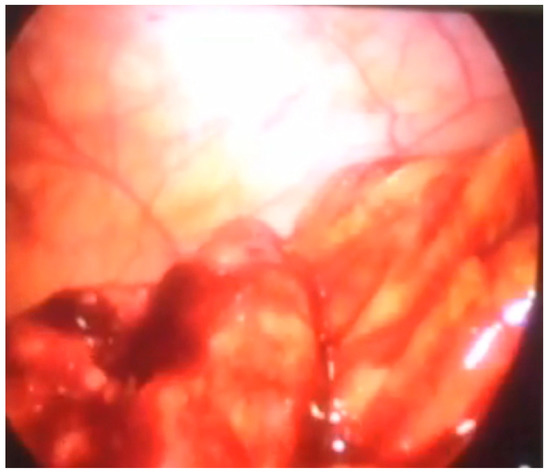

Another patient was hospitalized at our Institute due to abdominal pain and blood in a stool. A colonoscopy revealed a polyp in the region of the cecum. A simultaneous laparoscopic–endoscopic “rendezvous” polypectomy was performed, and the polyp was sent for histologic examination (Figure 6A). The polyp was on the long loop (Figure 6B) and the main difficulty was to differentiate the polyp from the edematous ileocecal (Bauhin’s) valve (Figure 7). The enterotomy on the cecum was sutured with direct intracorporeal sutures in two layers. The histology confirmed the diagnosis of a juvenile polyp.

Figure 6. (A) Laparoscopic excision of the cecum polyp, (B) polyp on the long loop.

Figure 7. Edematous ileocecal valve that could be missed for polyp.

A laparoscopic approach to treat polyps of the cecum is also rare in the literature [19]. Giavarini et al. [20] reported 15 patients with a median polyp size of 3 cm localized in the anterior, posterior and lateral wall of the cecum that were resected using a colonoscopy-assisted laparoscopic wedge resection (CAL-WR) with the success rate of 100%. This procedure with little modification is reported by Leicher et al. [19] for “difficult” polyps in terms of location—cecum, hepatic flexure, splenic flexure and sigmoid colon. Polyps of the cecum are considered and described in the literature as “difficult” because of their location and the proximity of the ileocecal valve [3]. These lesions were usually treated by open surgery, but nowadays, with the introduction of endoscopically assisted laparoscopic procedures, many of these lesions could be resected laparoscopically, as we described here. Our patient in whom a cecum polyp was identified, as reported in Case number nine, had no reported previous appendectomy; therefore, the possibility of a “stump” left after the appendectomy was rejected. The possibility of misdiagnosing the edematous ileocecal valve as a cecal mass is well documented since 1955 in terms of ileocecal prolapse [21], lateral position [22] or hypertrophy of the valve [23]. However, with the advancement of radiology and colonoscopy, misdiagnosing the ileocecal valve as a polyp is now minimal. The efficacy of every colonoscopy is now measured as a demonstration of the ileocecal valve and the detection of the polyps [24].